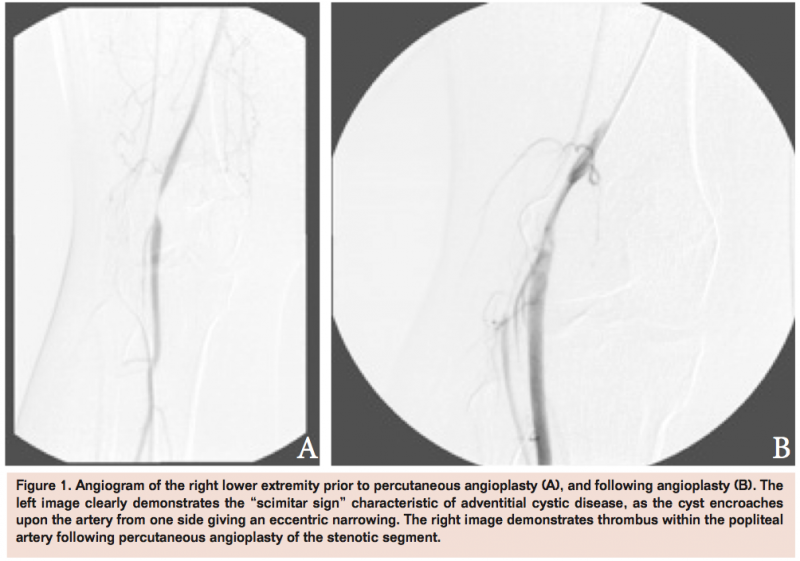

Noninvasive studies showed a normal ankle brachial index (ABI) on the right at 1.03 with the left ABI 1.37. However, diminished pulse volume recordings distally indicated some degree of arterial insufficiency of the right lower extremity. A right lower extremity angiogram revealed a smooth severe stenosis at the level of the popliteal artery (Figure 1A). The lesion was percutaneously angioplastied with a 5 mm balloon at 8 atm for 30 seconds, resulting in segmental thrombosis of the blood vessel (Figure 1B).

Several treatment modalities have been considered for treating adventitial cystic disease of the popliteal artery. As demonstrated in this case, an endovascular approach with percutaneous transluminal balloon angioplasty (PTA) is not an effective treatment. While it may appear attractive as endovascular technology continues to advance and expand treatment options, the method is plagued by a high recurrence rate and the literature repports suboptimal results.5 In perhaps the most dramatic demonstration that PTA does not provide lasting benefits in ACD, Khoury describes a case in which the popliteal artery stenosis recurred within 24 H of PTA therapy.3 Part of the failure of PTA as a treatment can be recognized in the pathology of the disease with the lack of involvement of the intimal layer. In ACD the mucinous cyst lies between the media and adventitia of the affected artery, providing external compression of the lumen.2,5 Luminal compression in PTA, even if able to elicit the release of cystic material, does nothing to treat the underlying disease process, making recurrence likely. It has also been noted that the affected vessels in cases of ACD are more compliant than atherosclerotic vessels, making them more likely than atherosclerotic vessels to re-stenose following dilation.5 However, even in cases in which PTA was coupled with intraluminal stenting, stenosis and symptoms of claudication have been noted to recur.6 Self-expanding stents may be another option, however limited information exists in the literature regarding use of these stents in this specific pathology. Perhaps the most compelling reason for avoiding the use of PTA, however, is the likely disruption of the healthy intima and subsequent thrombosis of the blood vessel, as was the case in our patient.